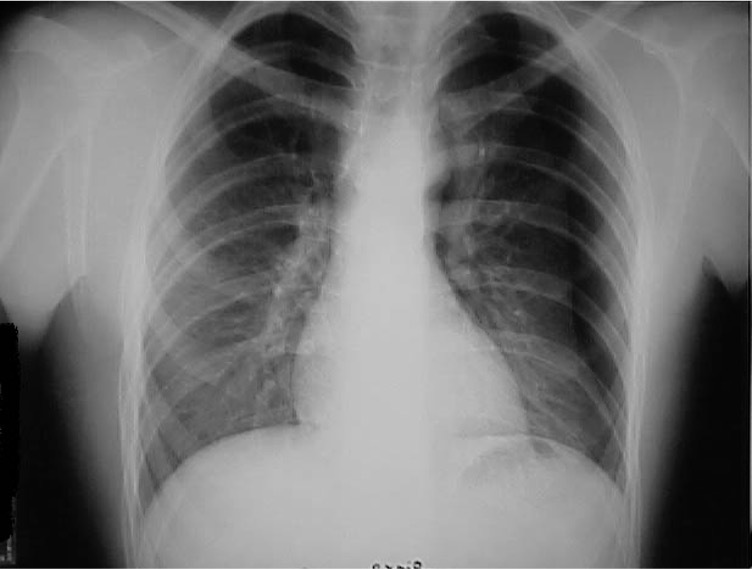

**Heart failure** Alveolar batwing shadowing Kerley B lines Cardiomegaly Upper lobe Diversion Pleural Effusion